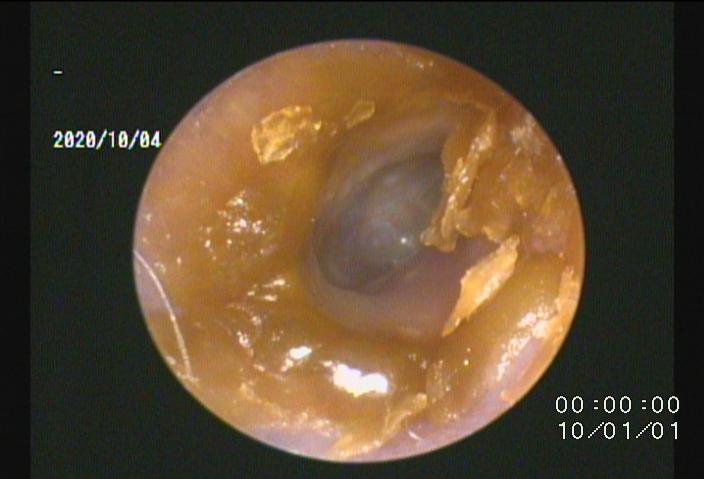

・当院では「耳道内視鏡」を導入し、今までは届かない部位で治療が困難であった鼓膜付近や中耳内、耳道壁の処置、徹底洗浄が可能です